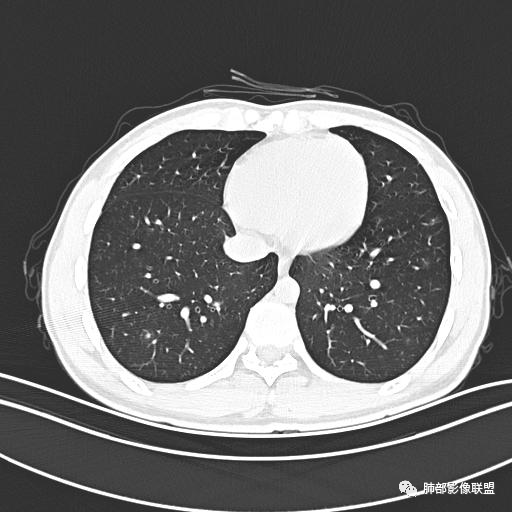

小强:青年,发热,皮疹;双肺散在结节,周围磨玻璃,点晕征,疱疹病毒感染,鉴别荚膜组织胞浆菌,结核。 大雄:青年,急性起病,发热伴全身皮疹2天,抗病毒治疗体温有下降。双肺随机分布大小不等类圆结节,“点晕征”。考虑水痘-疱疹病毒(VZV)血播询问接触史,查体皮疹分布以及形态基本可诊断。 王开金江津中心医院呼吸科:青年男性,起病急,病程短,以发热,皮疹为首发症状,感染指标以单核细胞升高为主,胸部ct双肺多发结界,周围有晕,点晕表现,随机分布,同意於老师意见,水痘疱疹病毒血流感染累及肺。 王秀仙:双肺多发大小不等结节,周围有晕,边缘模糊,呈点晕征表现。青年,急性起病,发热伴全身皮疹2天,抗病毒治疗体温有下降。考虑疱疹病毒。鉴别荚膜组织胞浆菌。 傅昌瑜:19岁男性,发热、全身皮疹2天,单核细胞增高,双肺多发结节,结节边缘见边界不清磨玻璃影。点晕征+发热、全身皮疹+单核细胞增高——考虑水痘-带状疱疹病毒肺炎。 一切∮随缘:年轻男性,发热,皮疹两天,实验室,CRP,PCT增高,影像:双肺多发散在磨玻璃结节,边界欠清,大小不等,呈点晕征改变,以血管束周围分布为主,局部血管束略增粗,其它无明显改变,考虑:1:病毒性肺炎(水痘疱疹病毒?不知道皮肤有无改变)2:真菌(组织胞浆菌,血管侵袭性肺曲霉)3:GPA4:寄生虫(实验室没有看到嗜酸细胞增高) 赵山河:双肺散在结节,周围有晕,边缘模糊,呈点晕征表现。青年,急性起病,发热伴全身皮疹2天,抗病毒治疗体温有下降。考虑水痘—疱疹病毒感染。洪桥爱:青年男性,发热、皮疹2天,伴瘙痒,皮疹于面部首发,之后进展至全身,虽然没有对皮疹进行描述,但是从出疹时间及皮疹进展情况,伴瘙痒,应该就是个水痘患者;CT提示双肺随机分布结节影,部分结节伴有边界不清晕征,考虑水痘血播肺。 刘强:年轻男性,急性起病,皮疹,发热,抗感染治疗体温下降,说明有效。影像表现为散在点晕征,感染类疾病谱(疱疹病毒,真菌,结核),结合年龄,皮肤皮疹,考虑水痘-疱疹病毒性肺炎。 小兜:男性,19岁,发热皮疹两天,颜面部至全身,CRP,降钙素及单核增高。CT示双肺散在小结节,周围伴磨玻璃影,点晕征,考虑为水痘-带状疱疹病毒(varicella-zoster virus,VZV)肺炎 必有路:青年,皮疹+发热+“点晕征”→水痘-疱疹病毒(VZV) 许慧良:青年男性患者,发热、皮疹2天,体温最高38.5℃,第3天皮疹扩展至全身,伴瘙痒,胸部CT:双肺多发随机分布的小结节,结节周边见边界模糊的晕征,考虑水痘病毒感染流心明智:男,19,急性起病,发热伴全身皮疹2天。出疹顺序头→全身,抗病毒有效。胸部CT:两肺多发大小不等类圆形实性小结节影,随机分布,结节周围环绕GGO,边界模糊,呈点晕征。出疹特点是关键,未提示。考虑:血播病毒性肺炎,水痘-疱疹病毒?麻疹?鉴别荚膜组织胞浆菌、TB、血管炎、寄生虫等。 浪迹天涯:病灶多为5-10mm大小结节,结节周围可见磨玻璃样的晕环,常多发,可分布于肺内任何区域,考虑水痘—带状疱疹病肺炎如果短时间内有新的一个区域浸润,更加能说明,